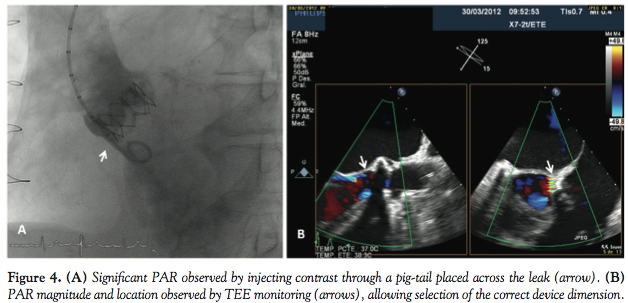

Two weeks after implantation, the patient was admitted to another hospital because of several episodes of typical chest pain at rest and symptoms of heart failure. The patient was re-transferred to our center for a new angiographic evaluation of coronary disease, grafts, and residual regurgitation. Echo study before catheterization showed a normal prosthetic function with mild anterior periprosthetic regurgitation. Angiographic evaluation confirmed no changes in coronary disease or patency of grafts and severe aortic insufficiency due to an anterior paravalvular leak (Figure 4A). TEE study confirmed the location and magnitude of the residual defect (Figure 4B).